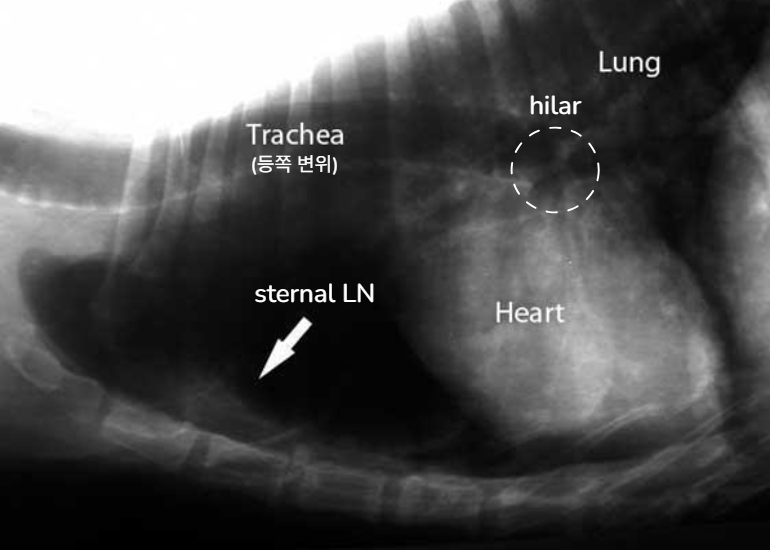

| Radiographs | |

![]() | ![]() |

| X-ray ์๊ฒฌ | ์์ธ |

|---|---|

| trachea์ dorsal variation | Mediastinal, hilar lymphadenomegaly |

| Sternal LN ์ดฌ์๋จ | Sternal lymphadenomegaly : MGT๊ฐ sternal ์ชฝ์ผ๋ก๋ ์ ์ด |

| descending colon์ ventral variation | Sublumbar lymphadenomegaly (์์ถํ ์ชฝ LN ๋น๋) |

| ์ฅ ์ชฝ์์ mass effect ์์์ ํฐ ๋ฉ์ด๋ฆฌ๊ฐ ์ดฌ์๋จ | Mesenteric lymphadenopathy (์ฅ๊ฐ๋ง ์ชฝ LN ๋น๋) |